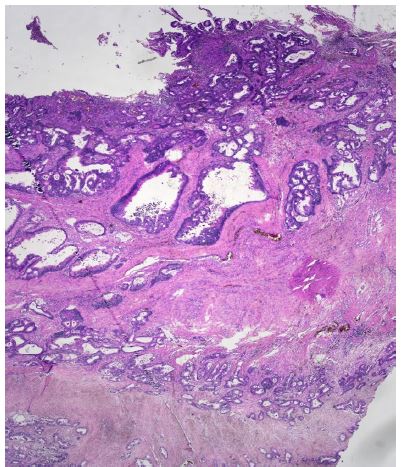

An abdominal Computed Tomography (CT) scan discovered a dilated colon up to the splenic flexure. A CT scan did not show regional nor distant metastases. Subsequently, the patient underwent exploratory laparotomy, which showed an obstructive tumour in the middle of the transverse colon, and there were no signs of macroscopic metastases in the abdominal cavity. The patient underwent resection of the transverse colon with end-to-end anastomosis. Postoperatively, the patient recovered well. Histopathological examination of the specimen revealed a moderately differentiated tubar adenocarcinoma, irregularly infiltrating the serosa, without lymphovascular invasion (Figure 1a), (T4a) and without nodal involvement (11 negative pericolic and 1 negative mesenteric lymph nodes were found); pT4a, N0, M0 (stage IIA); R0 resection was performed. Microsatellite instability-high (MSI-H) cancer was not proven.

However, based on the results of PET/CT, tumour marker elevation, malignant ascites, previous results and the course of the disease, the case was discussed at the colorectal MDT in the MMCI. The MDT recommended explorative laparotomy. In February 2018, surgery was performed with findings of a gastric lesion and multiple peritoneal metastases. Gastric resection in Billroth I modification with small and great curvature lymphadenectomy and omentectomy was performed, followed by cytoreductive surgery, resection of the peritoneum, and HIPEC for 90 minutes with cisplatin and mitomycin using Rand’s Performer HT device (Medolla, Italy). The postoperative recovery was uncomplicated, and the patient was discharged on the eleventh postoperative day. Histologic examination found metastases of moderately differentiated adenocarcinoma of colorectal origin with perineural invasion in the gastric antrum wall without mucosal changes (Figure 1c). Six lymphatic perigastric and five omental lymph nodes were harvested, and all nodes and peritoneal strips were negative for cancer. Adjuvant chemotherapy based on capecitabine and oxaliplatin (XELOX) was administered and the patient was followed in four-month intervals.

Figure 1a: Microscopic histological findings. A resected specimen of the sigmoid colon showed an irregular ulcerated lesion. A histological examination of the resected specimen of the sigmoid colon revealed a moderately differentiated adenocarcinoma invading the subserosal layer. (×100 magnification; haematoxylin and eosin stain).

Figure 1b: Microscopic histological findings. A resected specimen of the sigmoid colon showed an irregular ulcerated lesion. A histological examination of the resected specimen of the sigmoid colon revealed a moderately differentiated adenocarcinoma invading the subserosal layer. (×100 magnification; haematoxylin and eosin stain).

Figure 1c: Microscopic histological findings. A resected gastric specimen showed a moderately differentiated intestinal adenocarcinoma without mucosal changes. A low- and high-power microscopic view of the mass in the stomach revealed moderately differentiated adenocarcinoma (×100 magnification; haematoxylin and eosin stain).

Figure 1d: Microscopic histological findings. A resected specimen of the abdominal wall showed a moderately differentiated intestinal adenocarcinoma (×100 magnification; haematoxylin and eosin stain).